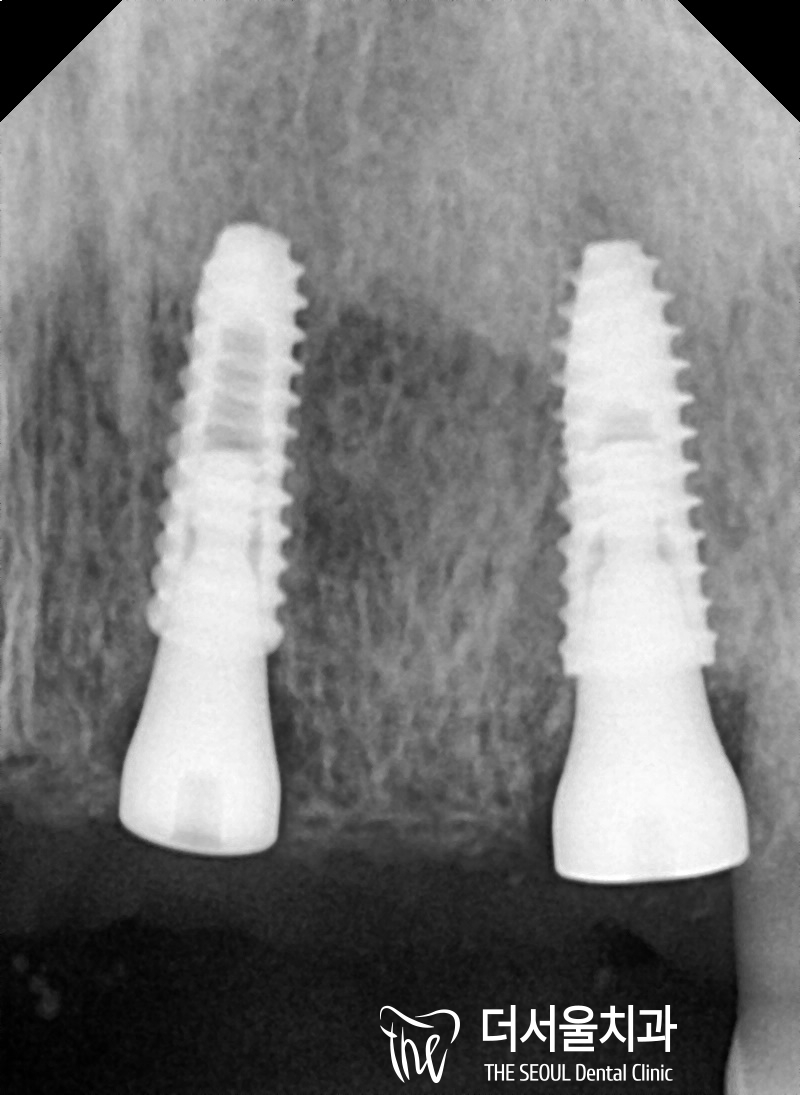

3차원으로 분석을 마친 뒤에는

제작된 가이드를 사용하여 식립을 마쳤습니다.